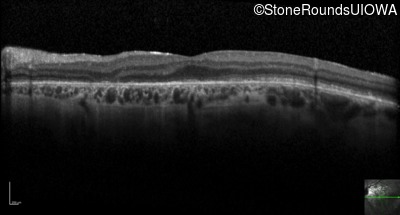

Optical Coherence Tomography - Right - 20/100 +1

Exemplar / OCT Stack